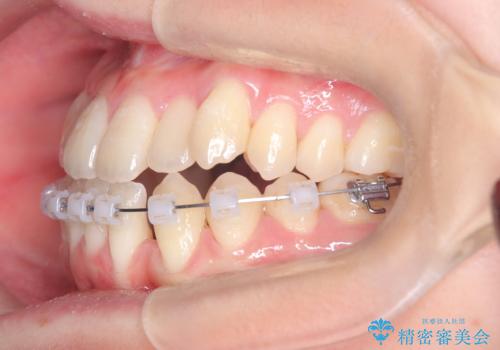

安全かつ確実に抜歯スペースを閉じ、咬み合わせを完成させるため、マウスピースから**ワイヤー矯正(マルチブラケット装置)**へ切り替えるリカバリープランを提案しました。

装置の変更と歯肉への配慮: ワイヤー矯正は歯の根(歯根)を平行に移動させる「歯体移動」を得意としています。本症例では、歯肉退縮を防ぐために、歯の傾きを精密にコントロールしながら抜歯スペースを閉じる必要がありました。ワイヤー装置を用いることで、インビザラインでは難しくなっていた三次元的な細かい調整を可能にしました。